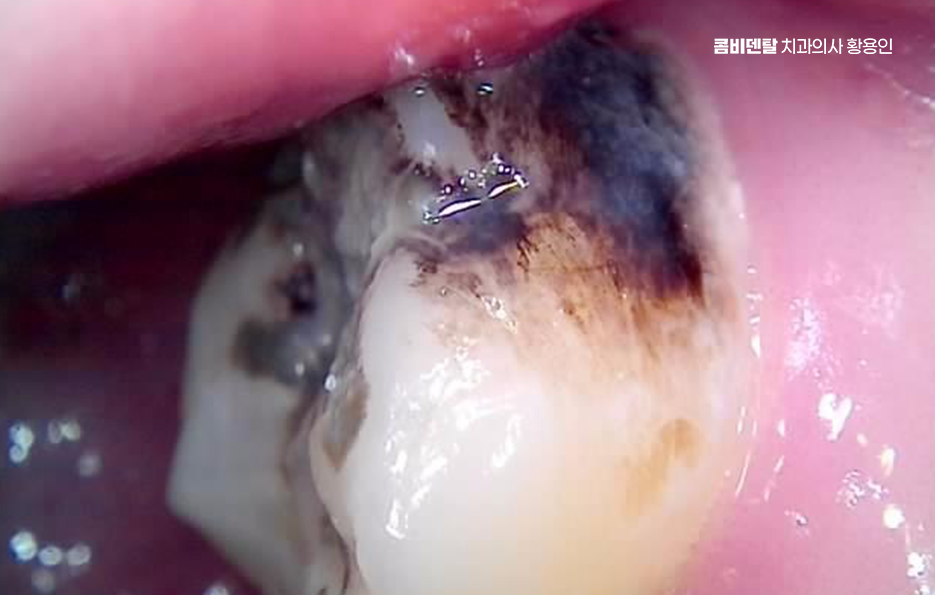

통증이 더 강하고 오래 지속된다면 염증으로 인한 신경 감염을 의심해볼 수 있으며 충치가 깊어져 신경 가까이까지 진행되면 차갑거나 뜨거운 자극에 강한 통증이 나타날 수 있어요.

초기에는 자극이 사라지면 통증도 금방 사라지지만, 염증이 심해지면 자극이 없어도 계속 아플 수 있으며 밤에 더 심해지는 통증은 신경염의 특징 중 하나로 이 단계에서는 단순 충치 치료가 아니라 신경치료가 필요할 수 있어요.

신경 염증이 원인이라면 원인에 대한 치료를 통해 해결해야 하는데 충치를 제거하고 신경 상태를 평가해 신경치료 여부를 결정해야 하며 이미 신경이 괴사된 경우에는 신경을 제거하고 내부를 소독한 뒤 밀봉하는 과정을 거치며 이후에는 치아가 약해지지 않도록 크라운을 씌워서 보호하는 치료 방법이 있어요